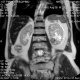

Мужчина, 1942 года.Жалоб нет.

постконтраст

"прекрасная" левая почка. Мужчину совсем ничего не боспокоит?

Ничего -со слов.Пришел провериться , без направления.

Влевой почке опухоль. А  прямой кишке по правой стенке?

Написала тканевое образование,порекомендовала дообследование. А мочевой не смущает?